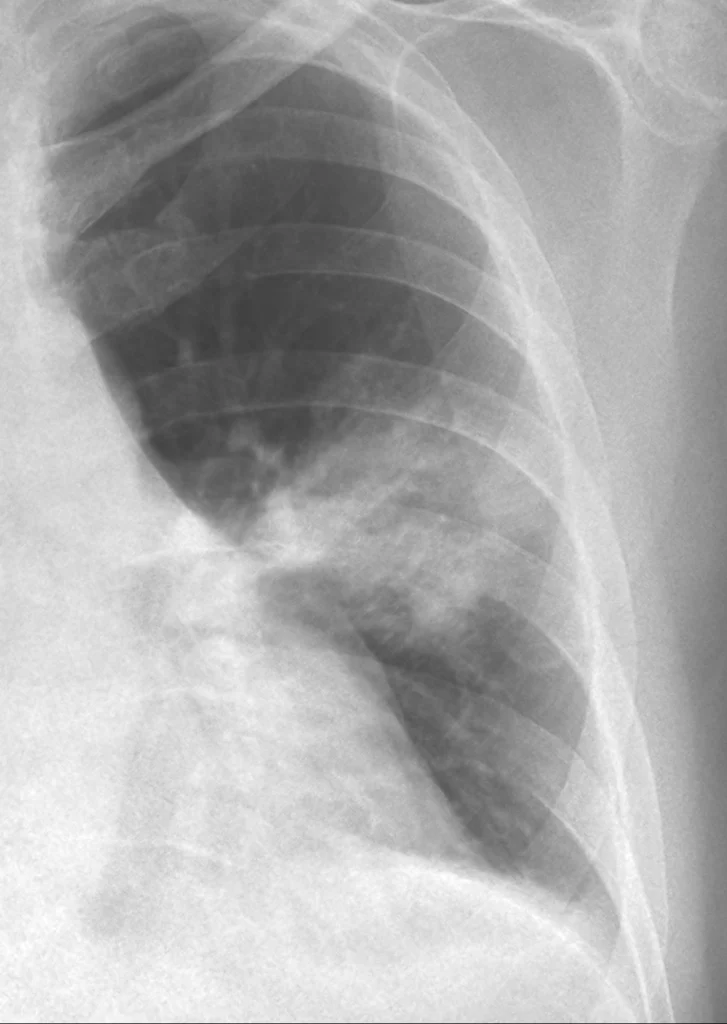

Esquema que representa la absorción de los rayos X y su traducción en la imagen radiológica. Discusión del caso Esquema que representa la absorción de los rayos X por los distintos tejidos, la radiación transmitida y su traducción en la imagen radiológica. Si las estructuras evaluadas tuvieran idéntico espesor, la absorción de la radiación dependería […]